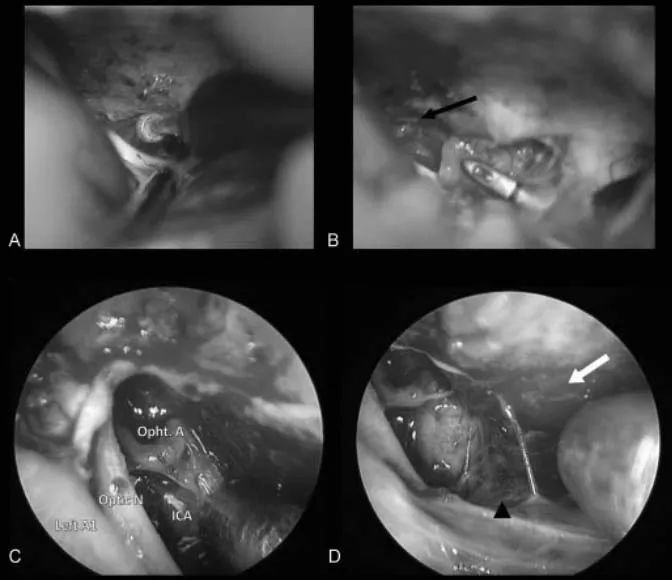

手术过程:一阶段,通过钻取蝶缘和内侧视神经管进行视神经减压术,为后续手术做准备。二阶段经,经额下入路为对侧交叉沟和视神经提供绝佳手术通道,可以保障顺利切除肿瘤。

图4:术中照片。(A)早期视神经减压术和管内肿瘤的暴露是通过磨除蝶缘和内侧视神经管来完成的。(B)直接切除肿瘤,同时识别和保护眼动脉(黑色箭头)。(C)内镜下直视神经管。(D)使用30度角内镜查看其它潜在潜在的硬膜区域(白色箭头),如果发现,可以电凝处理。ICA,颈内动脉;Left A1,左大脑前动脉;Opht.A,眼动脉;Optic N,视神经。

术后结果:艾琳的肿瘤完全切除(辛普森II)(图5),术后视觉好转,嗅觉功能无损害/无脑脊液渗漏。